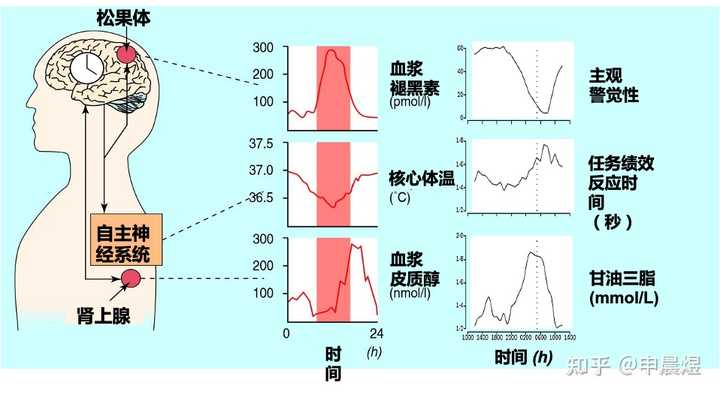

也称为“生物钟”,是机体内部发生的周期性变化过程,最典型的例子是睡眠与觉醒的周期性交替。昼夜节律(circadian rhythms) 是生物节律之一,是有机体在生物钟控制下产生的生物化学、生理学、行为模式的24h循环周期[1]。大多数生理和行为是由下丘脑生物钟控制的,分子钟作用于神经和内分泌通路,调节个体的生物节律,使机体在24h内适应外部环境的改变,并通过合成代谢和分解代谢来提高机体运转的效率[2]。

生物节律紊乱使抑郁症风险升高

睡眠和生物节律紊乱(SCRD)是21世纪普遍特征,对轮班工人的研究表明,SCRD不仅导致认知障碍,还会导致代谢综合征和抑郁症等精神障碍[3]。

生物节律紊乱引发的睡眠障碍持续存在,可导致抑郁复发风险增高[4]。

与昼夜节律正常的同龄人相比,节律延迟的个体抑郁症状更严重,且更易出现轻度躁狂症状[5]。

抑郁症可致生物节律相位延迟

抑郁患者的生物节律往往是相位延迟的,意味着早上觉醒度不足,晚上入睡困难。难以入睡进一步加剧了白天的困倦感[7]。

抑郁症患者的睡眠结构节律紊乱[8]